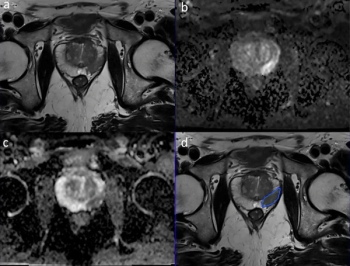

Study: MRI-Based AI Enhances Detection of Seminal Vesicle Invasion in Prostate Cancer